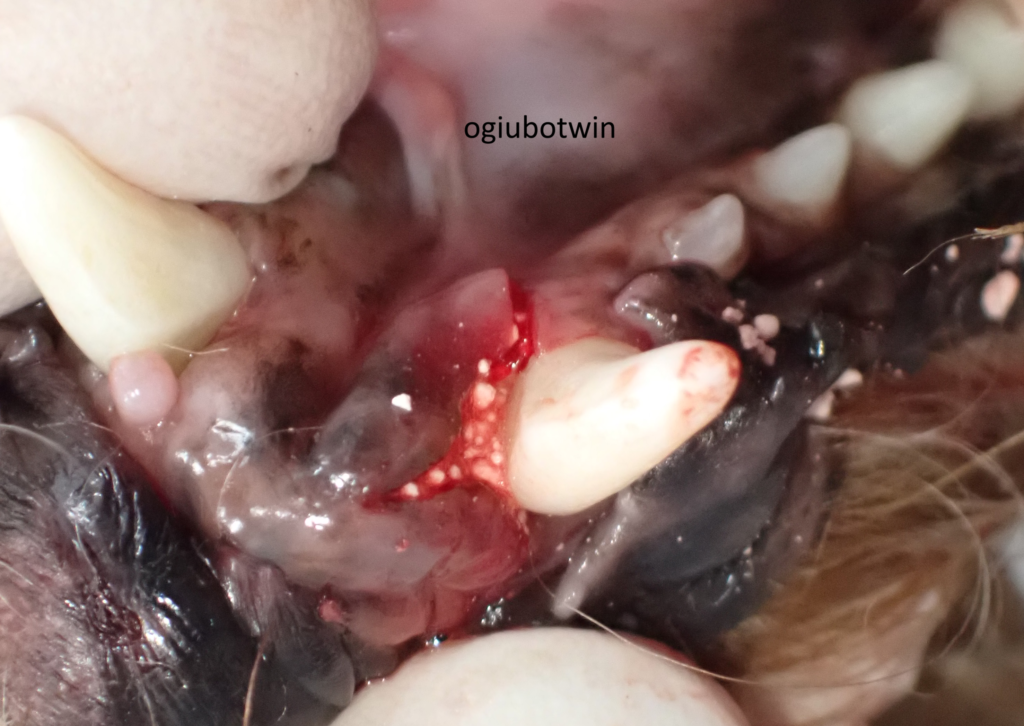

左下顎の犬歯は歯周ポケットも深く、再生治療を行わないと残せないと判断しました。

左の下顎犬歯は舌側、頬側ともに切開したフラップを閉じるのが困難だったため、中央に切開を入れ、歯根によるように剥離しました。

骨をなるべく露出した状態で、β-TCPを混ぜたエムドゲインを最深部に注入し充填し、縫合しました。